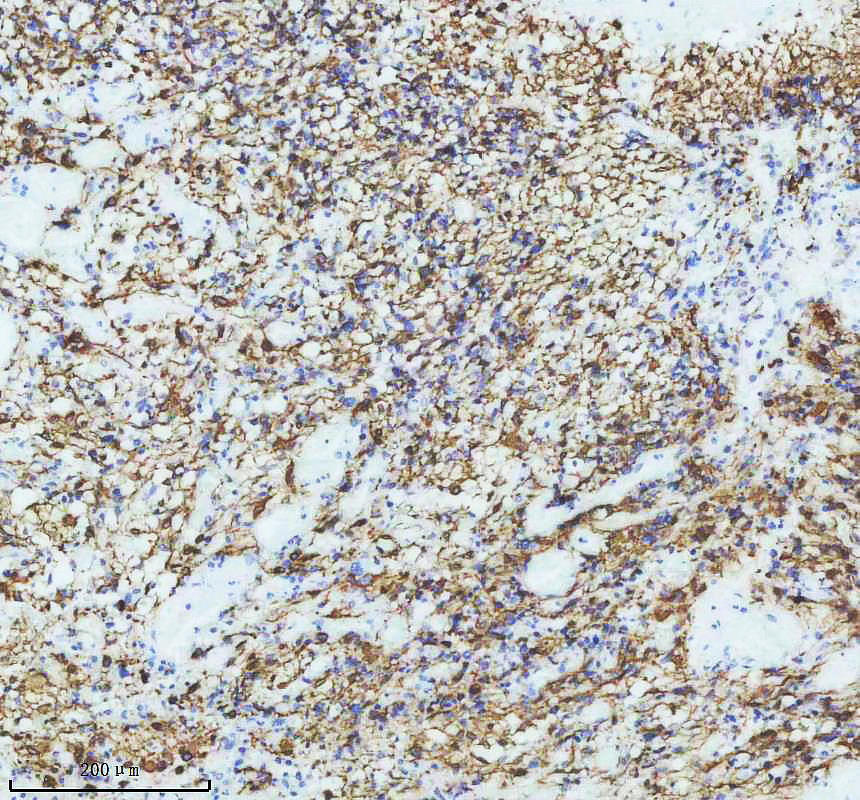

IHC analysis of GFAP using anti-GFAP antibody (BM4287) .

GFAP was detected in a paraffin-embedded section of human glioma tissue. The tissue section was incubated with rabbit anti-GFAP Antibody (BM4287) at a dilution of 1:200 and developed using HRP Conjugated Rabbit IgG Super Vision Assay Kit (Catalog # SV0002) with DAB (Catalog # AR1027) as the chromogen.